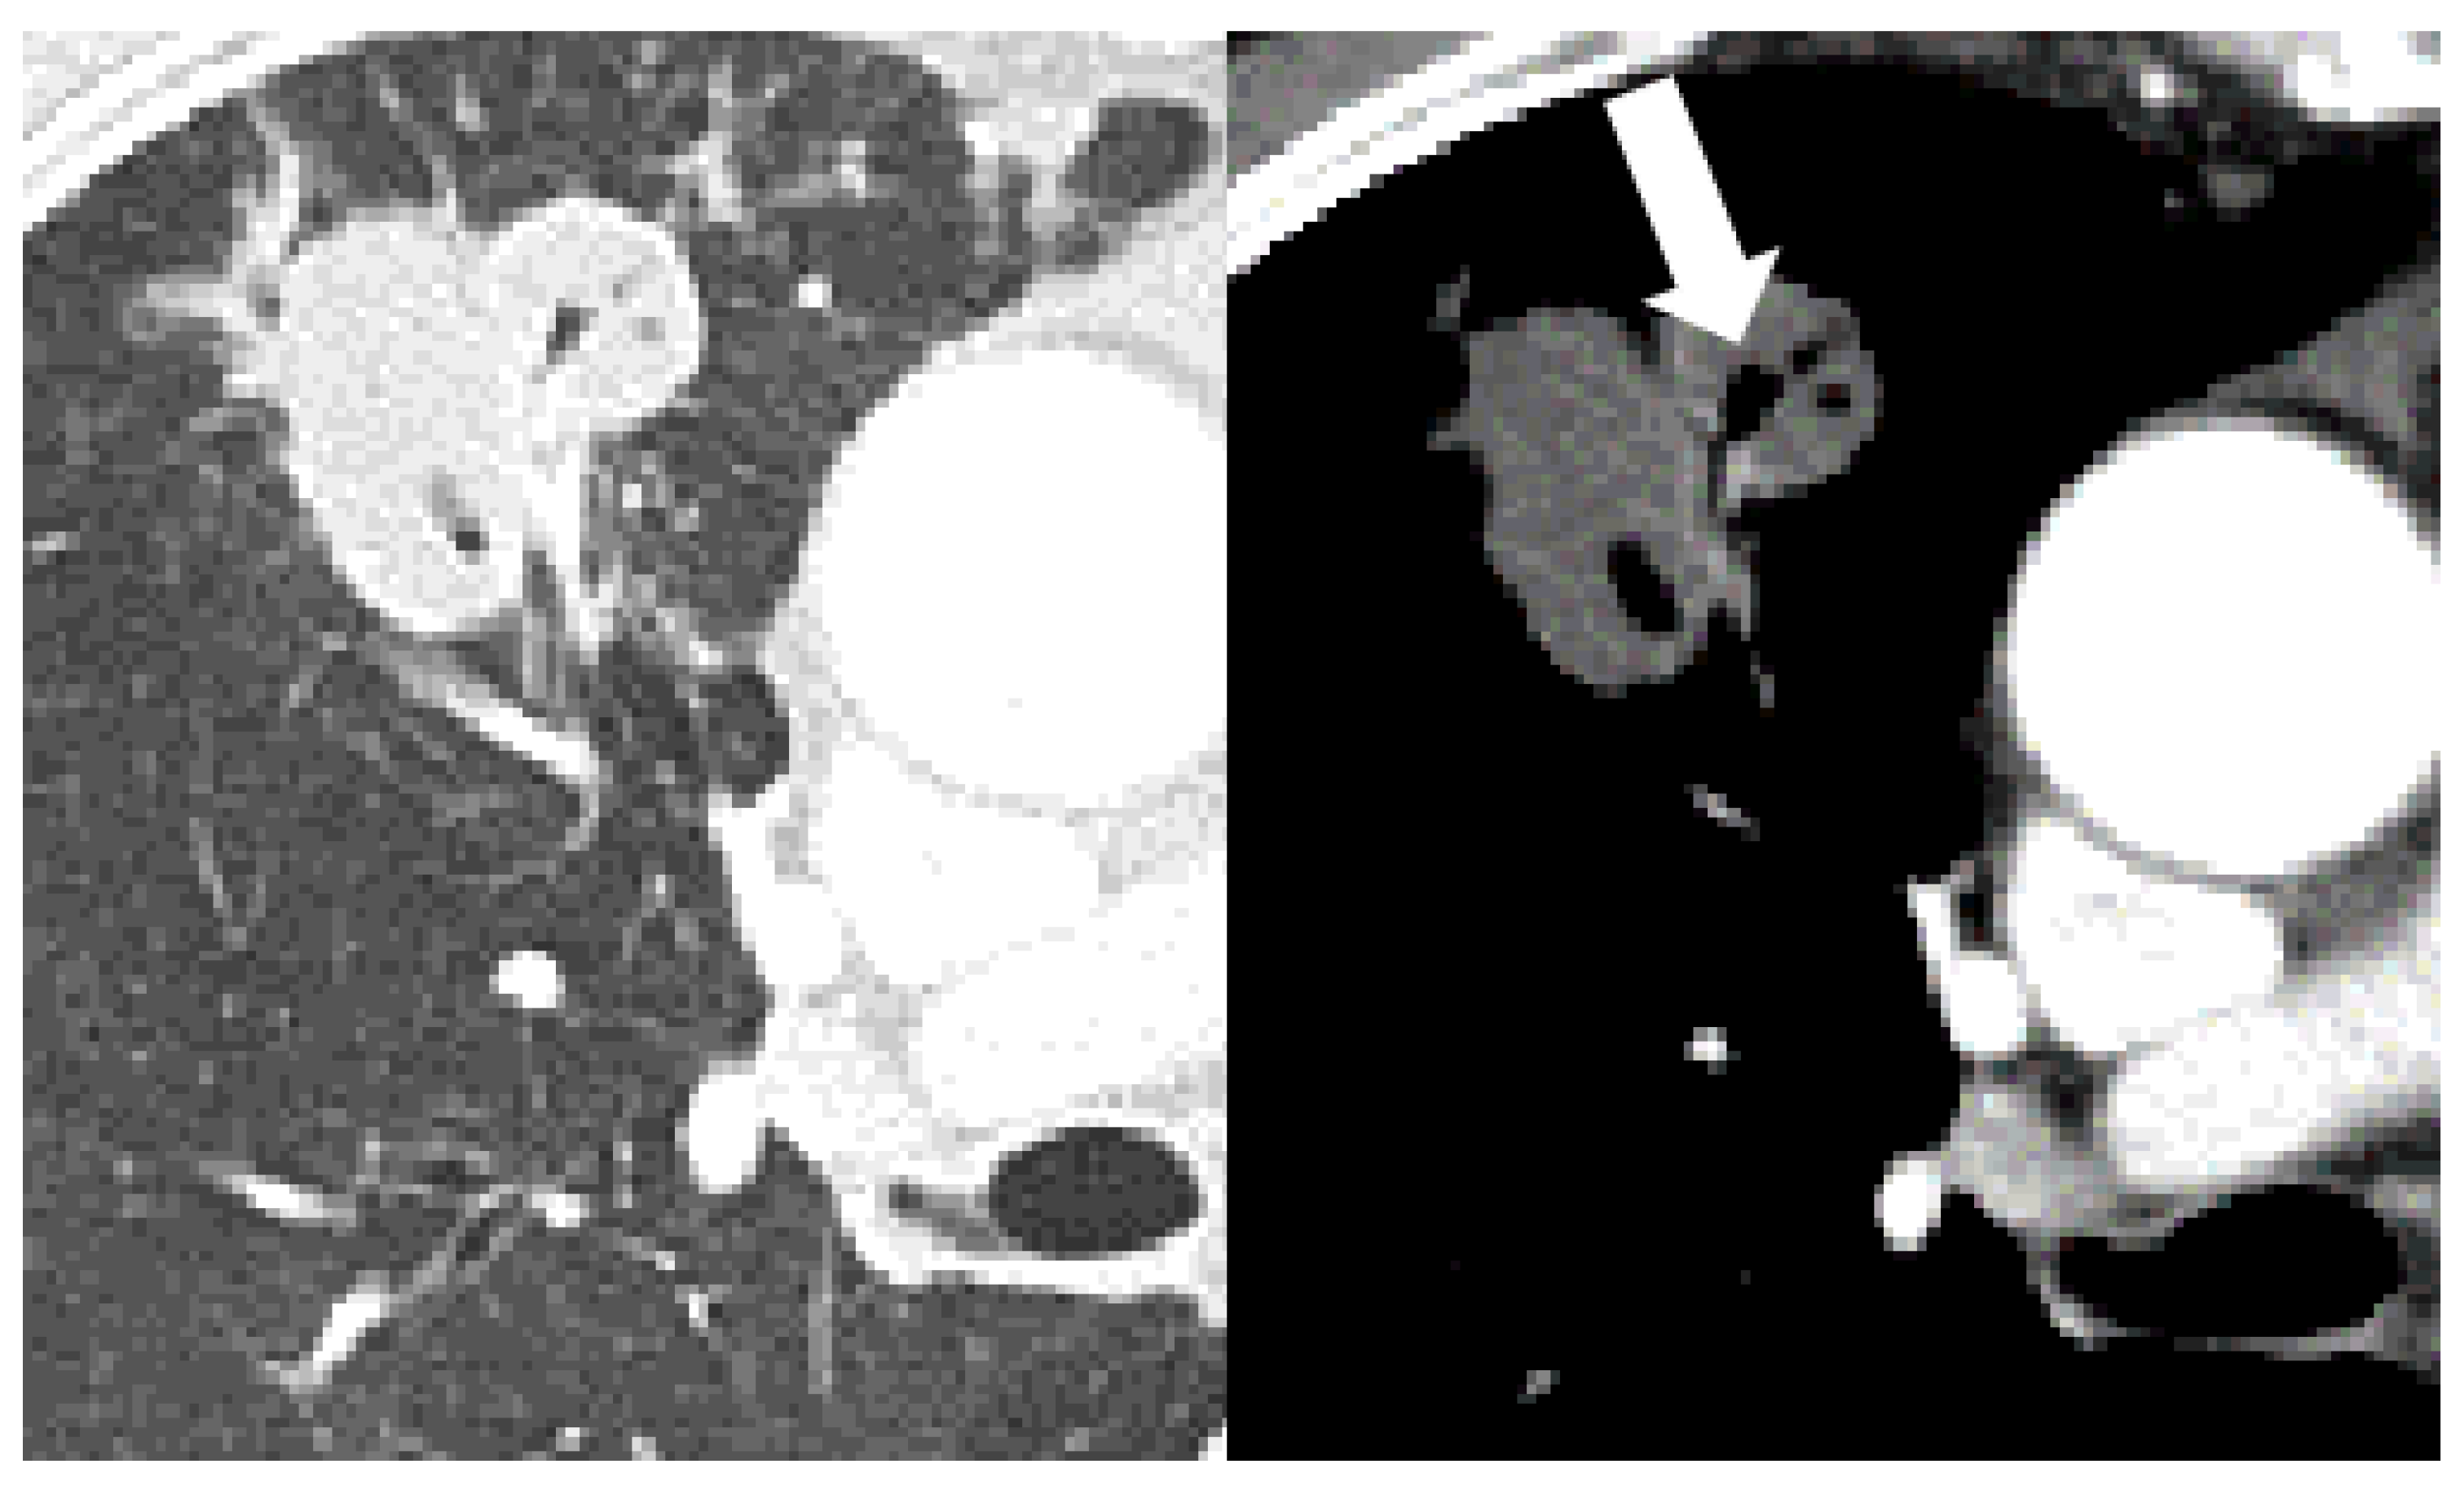

| Cavitation | 157 (47) | 109 (43) | 7 (23) | 41 (79) | <0.001 | 0.038 | <0.001 | <0.001 |

| Bronchial erosion | 157 (47) | 110 (44) | 9 (30) | 38 (73) | <0.001 | 0.157 | <0.001 | <0.001 |